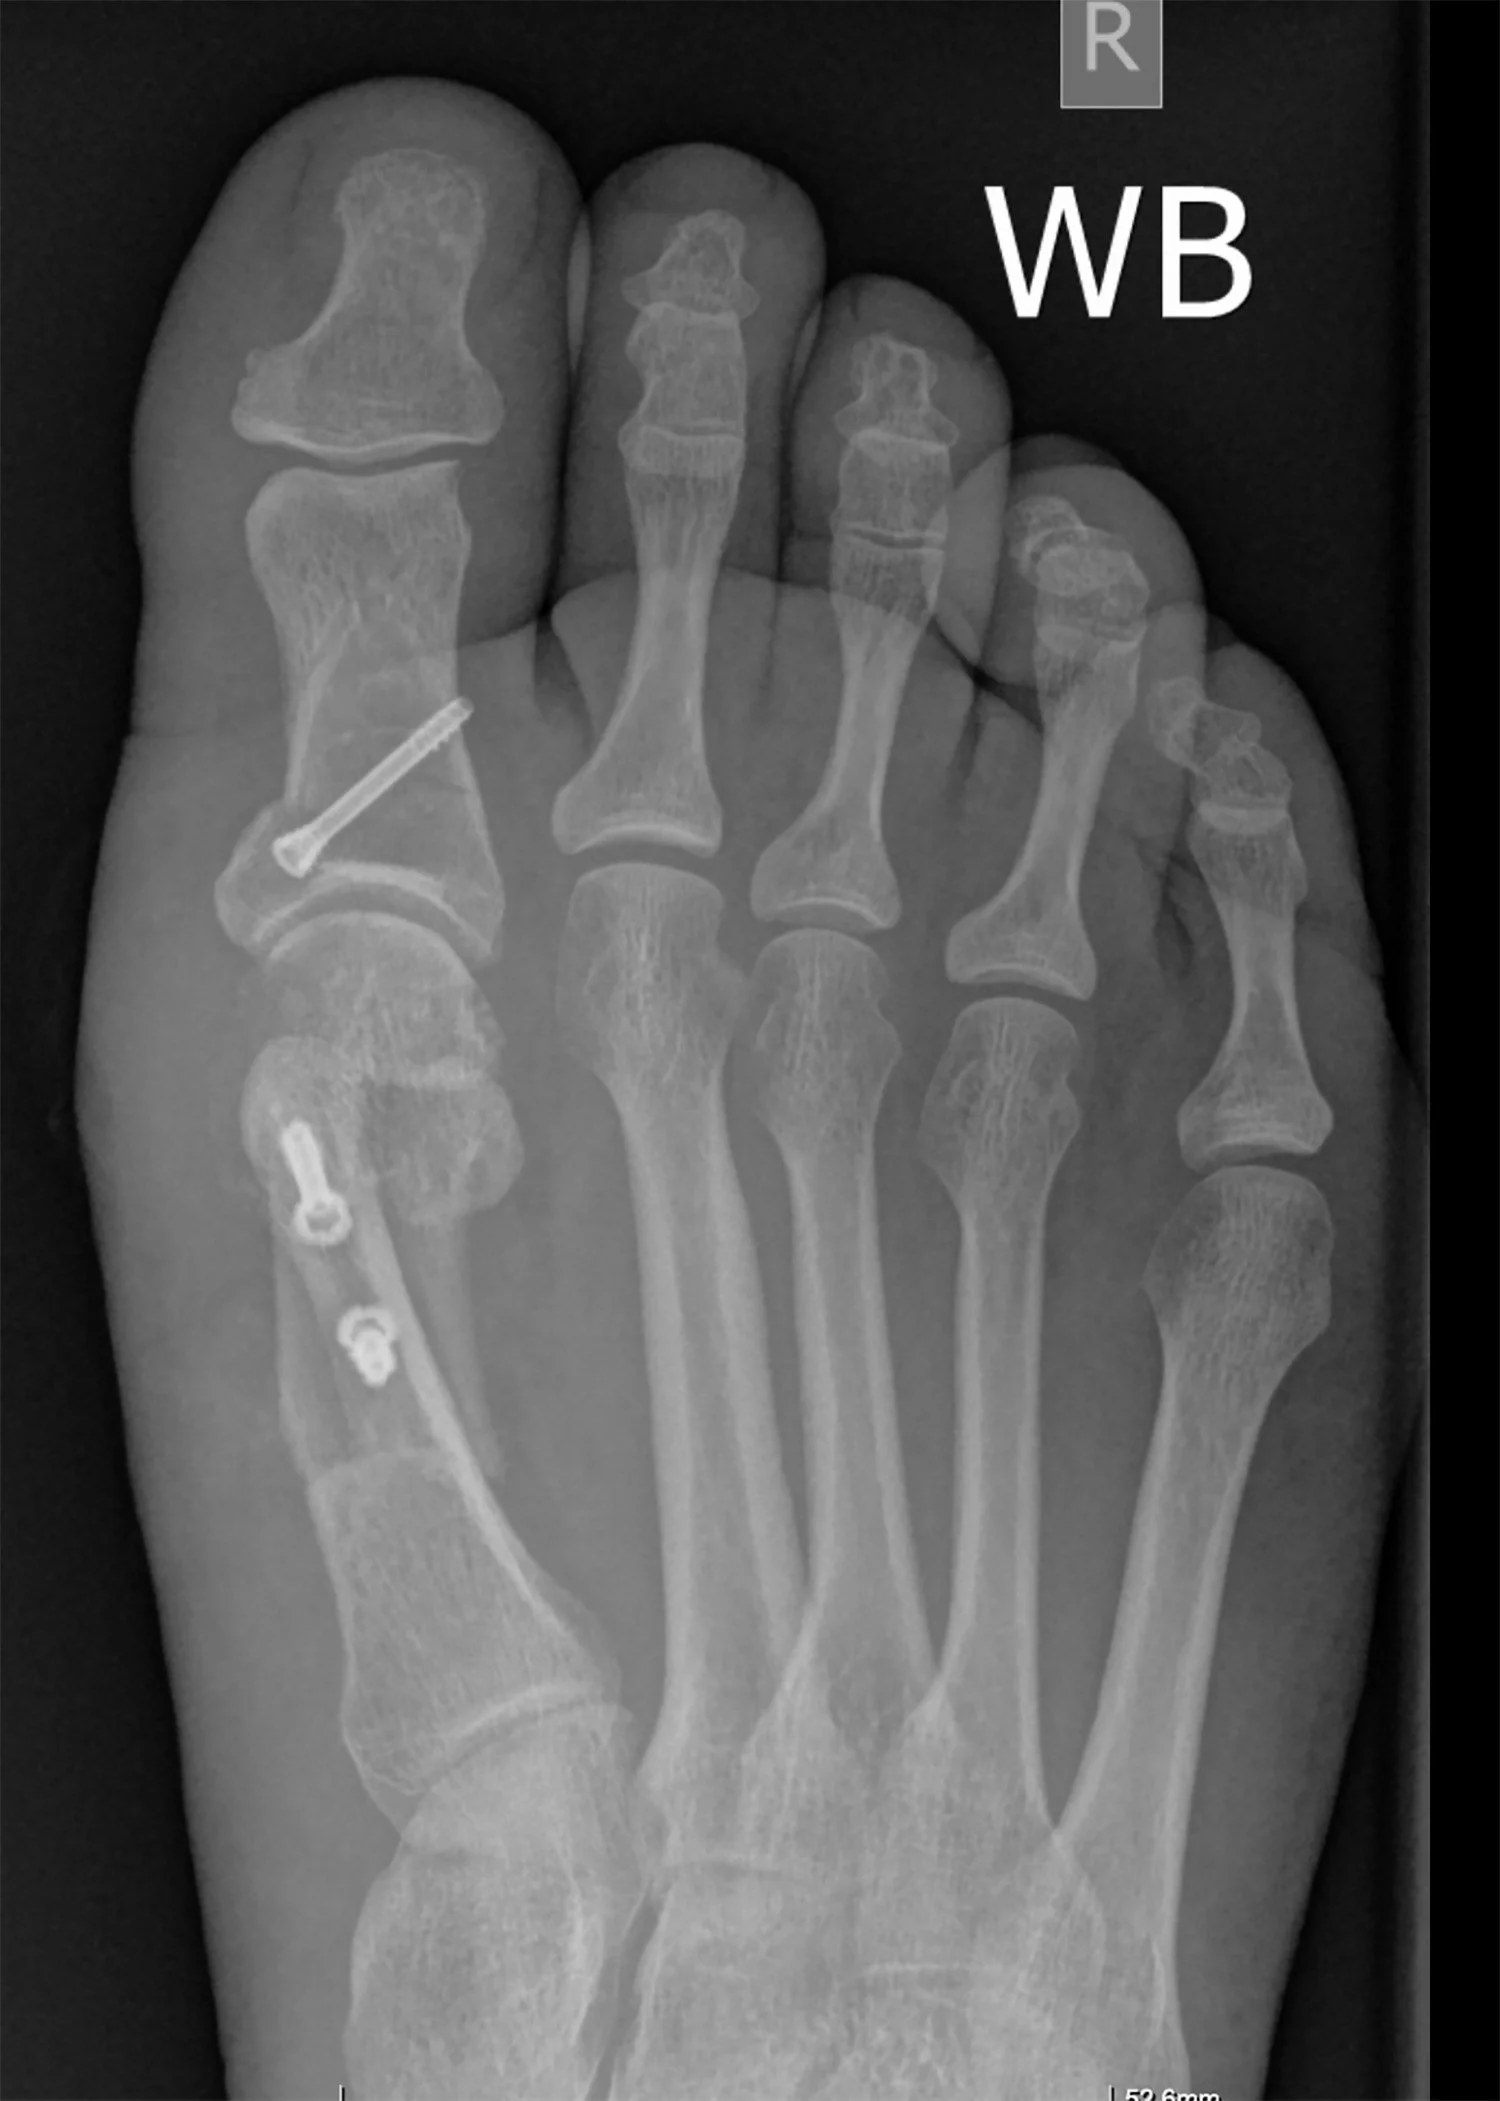

Procedure

Fixation

Internal fixation (bone screws, plates or wires) are usually used.

You will not normally notice these and they do not usually need to be removed (<20%).